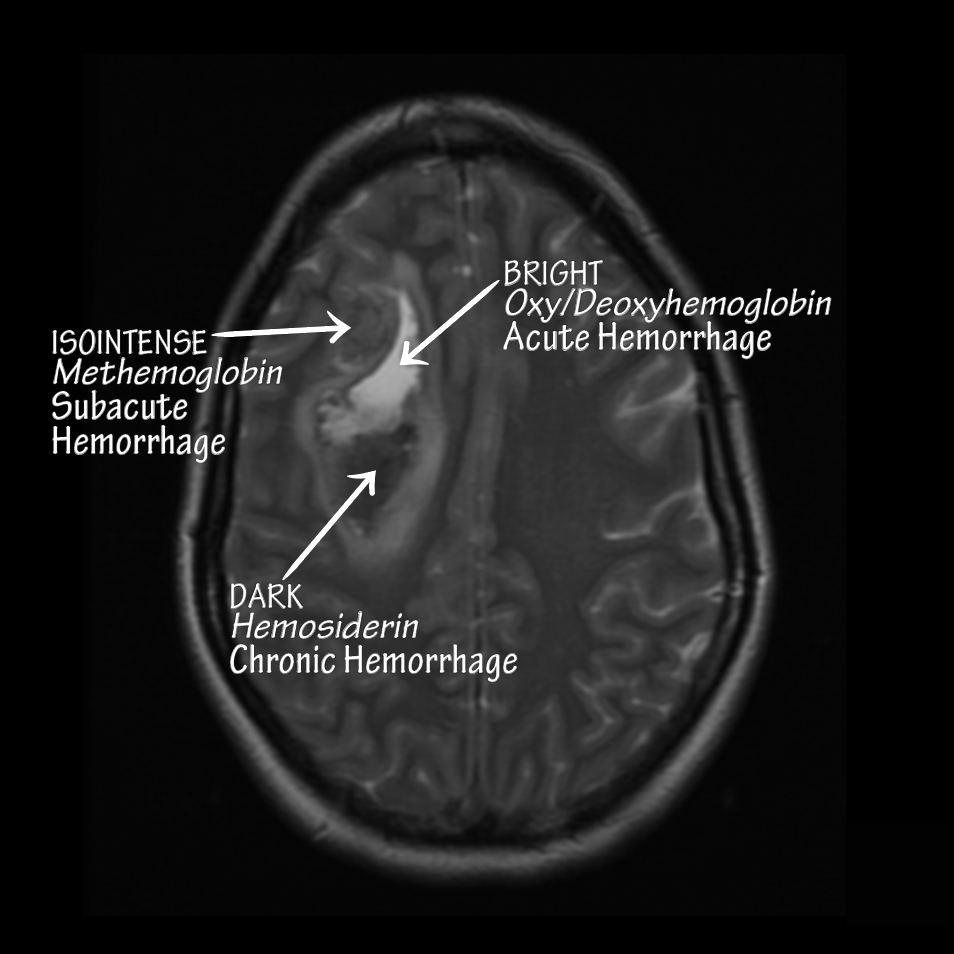

Various blood products on Axial MRI of an intraparenchymal hemorrhage.

• MRI characteristics: popcorn-shaped lesions with varying signal intensities secondary to different ages of blood products (see: MRI: Heme Products).